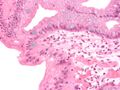

Micrograph of Barrett's esophagus, an example of glandular metaplasia.